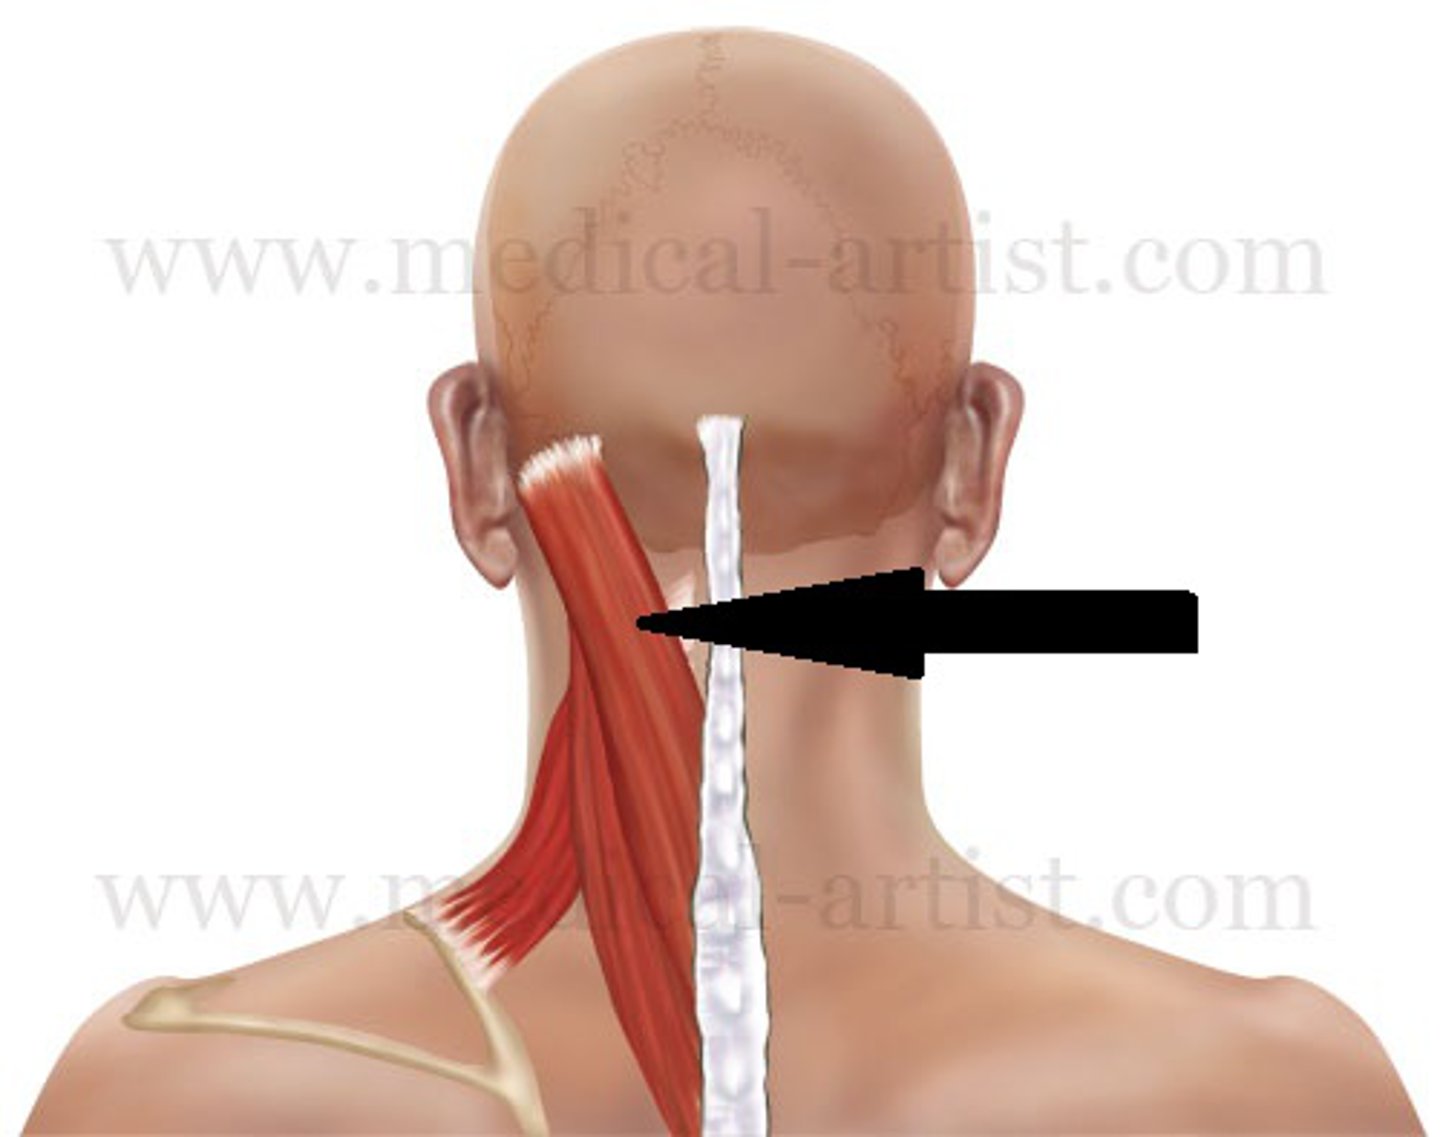

Sternocleidomastoid

Located at the base of your skull on either side of your neck, behind your ears. On both sides of your neck, each muscle runs down the front of your neck and splits to attach to the top of your sternum and collarbone.

Trapezius

A large paired surface muscle that extends longitudinally from the occipital bone to the lower thoracic vertebrae of the spine and laterally to the spine of the scapula

Splenius Capitus

Deep to sternocleidomastoideus at the mastoid process, and to the trapezius for its lower portion. It is one of the muscles that forms the floor of the posterior triangle of the neck